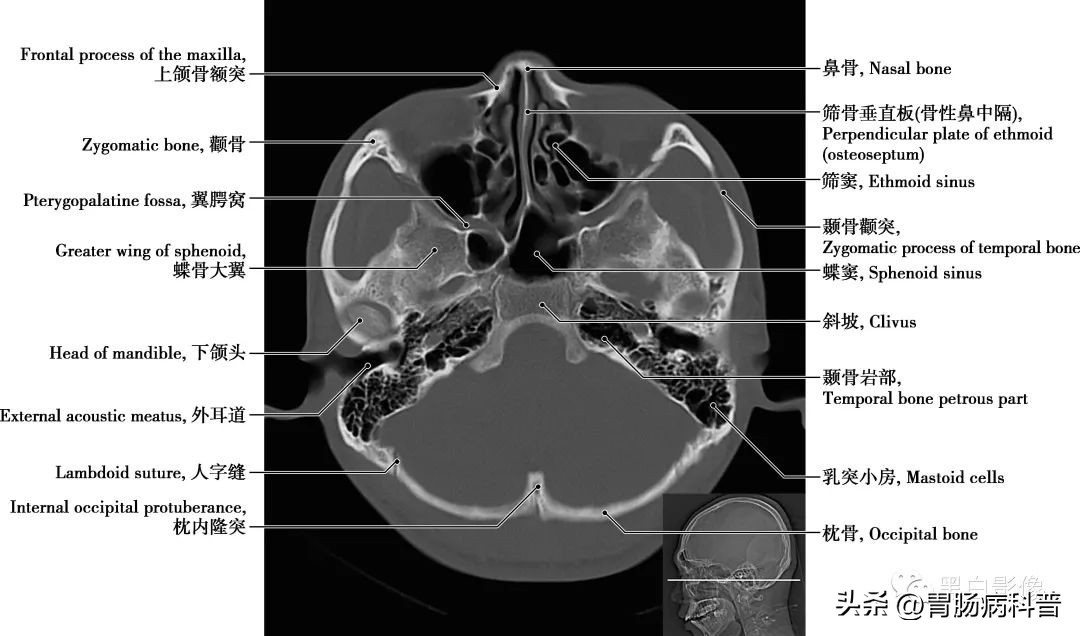

图1-2-18 经下颌头轴位切面

卵圆孔和棘孔 在蝶骨大翼近根部处由前向后可见圆孔、卵圆孔和棘孔,圆孔内走行上颌神经,卵圆孔内走行下颌神经,棘孔内走行脑膜中动脉。颈动脉管 是颈内动脉进入颅腔的管道,在颞骨岩部内弯曲形成一定角度,再经颈动脉管内口于破孔处离开颈动脉管进入颅内

图1-2-19 经小脑扁桃体轴位切面

上颌窦 上颌骨体内的锥形空腔,位于上颌骨体内,窦壁为骨质,窦壁覆黏膜,向内侧开口于中鼻道,分为一底、一尖及前、后、上、下四个壁。由于窦口高于窦底部,故在直立位时若有炎性物不易自然流出。鼻泪管 为一膜性管道,上部包埋在骨性鼻泪管中,与骨膜紧密相结合;下部在鼻腔外侧壁黏膜深面,下部开口于下鼻道外侧壁的前部